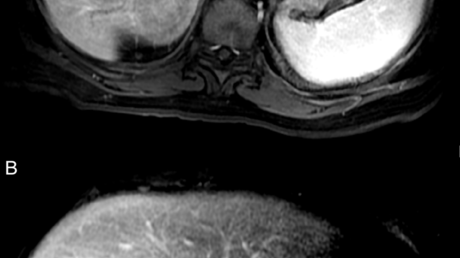

Cureus | Red Dot Basal Cell Carcinoma: Report of Cases and Review of This Unique Presentation of ...

Cureus | Red Dot Basal Cell Carcinoma: Report of Cases and Review of This Unique Presentation of ... from assets.cureus.com